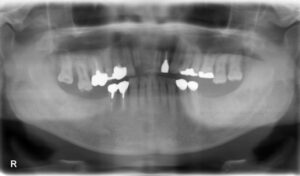

下顎臼歯4本欠損症例

BEFORE AFTER 52歳女性/下4本欠損/インプラント埋込手術 【治療内容】 左下第二小臼歯、第一大臼歯、第二大…